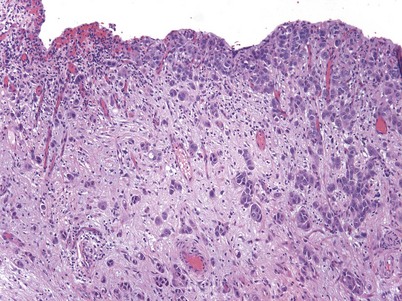

Non–muscle-invasive bladder cancer (NMIBC) includes CIS, papillary urothelial neoplasia of low-malignant potential (PUNLMP), and low- and high-grade urothelial cancer that previously had been called “superficial bladder cancer,” which is a misnomer. The clinical significance of the WHO grading classification is shown in Table 80–6. The grade distribution of NMIBC is 25% PUNLMP, 50% low grade, and 25% high grade (including CIS) (Holmang et al, 2001; Samaratunga et al, 2002). CIS is characterized as nonpapillary, flat, high-grade tumors in which the surface epithelium contains cancer cells (Fig. 80–8) (Sauter et al, 2004). There is severe nuclear atypia, loss of cellular polarity, and a noncohesive cellular structure. The cells are large, pleomorphic, chromatin clumping, and abnormal mitotic figures are common. Loss of umbrella cells is a characteristic, separating CIS from dysplasia. All CIS is high grade by definition. The genetic abnormalities associated with CIS include alterations to the RB, TP53, and PTEN genes (Cordon-Cardo et al, 2000; Lopez-Beltran et al, 2002; Cordon-Cardo, 2008). CIS is immunoreactive for cytokeratin 20, and NMP22 is present in the cells. CIS is a precursor lesion for invasive cancer and can spread to the distal ureters and prostatic urethra on the surface or in a pagetoid manner, undermining normal adjacent urothelium (Montironi et al, 2002). Endoscopically, CIS is reddish with heaped-up mucosa and can be mistaken for inflammatory changes or radiation cystitis. CIS in association with invasive tumors have a worse prognosis, with a 45% to 65% 5-year death rate (Lopez-Beltran et al, 2002).